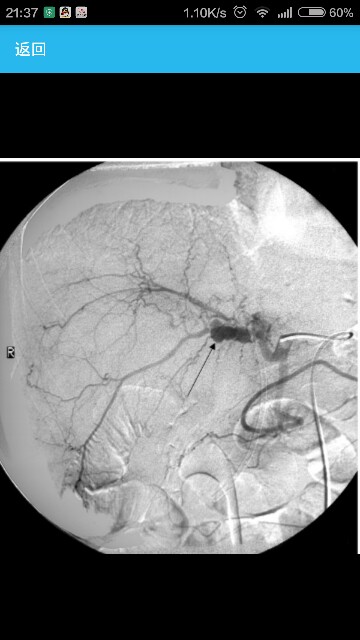

患者,男,38岁,患者10个月前无明显诱因出现发热,Tmax 38℃,发热无明显规律,否认畏寒、寒战、乏力、盗汗,否认咳嗽、腹痛、腹泻、尿频、尿痛,无皮疹和关节肌肉痛。在当地诊所查血白细胞(WBC)11.2×109/L,中性粒细胞(Neut)82.8%,给予头孢类抗生素治疗效果不佳。当地医院考虑"结核",予以异烟肼、利福平、吡嗪酰胺抗结核治疗5个月,效果不显著,仍有发热。 临床表现发热10个月,伴腰痛、腹痛2个月。 血常规WBC(8.10~10.9)×109/L(正常值4.0×109~10.0×109/L),Neut 73.5%~76.4%(50%~75%),血红蛋白(Hb) 107~110 g/L(男120~165 g/L),血小板(Plt) (427~489)×109/L[(100~350)×109/L];尿常规、便常规+隐血均阴性。肝肾功能、肌酶谱正常;血沉(ESR)53 mm/1h(男<15 mm /1h),C反应蛋白(CRP) 69.3 mg/L(0~8.0 mg/L)。感染方面:乙肝五项、快速梅毒血清反应(RPR)、抗EB病毒抗体(EBV-Ab)、抗丙型肝炎病毒抗体(抗HCV)、抗人免疫缺陷病毒抗体(抗HIV)、布氏凝集试验均阴性,骨髓培养阴性×1次。肿瘤标志物:血癌胚抗原(CEA)、糖链抗原CA19-9、CA125、CA242、CA50和甲胎蛋白(AFP)均正常。结缔组织病方面:抗核抗体(ANA)、抗双链DNA抗体(抗ds-DNA)、抗中性粒细胞胞浆抗体(ANCA)、人类白细胞抗原(HLA-B27)均阴性。胸片(-)。超声心动图(UCG):无心包积液,主动脉后壁及左房侧壁外可见中等度强回声。腹部超声(-)。 多发大动脉动脉瘤,系统性血管炎。 患者为诊断:多发大动脉动脉瘤诊断明确,有发热,ESR、CRP等炎症指标增高,考虑有系统性血管炎的可能,病情活动,动脉瘤形成时动脉壁撕裂引起腰痛、腹痛。累及大动脉的血管炎病变有:(1)Takayasu动脉炎,又称无脉症,多发生在女性,引起动脉闭塞,引起动脉瘤较少见。(2)巨细胞动脉炎,多见于老年人,有头痛、咀嚼无力、视力受损等症状,该患者的临床表现不支持。(3)白塞病(Behcet's disease),需要再仔细询问有无口腔、外阴溃疡和眼葡萄膜炎病史。 治疗让患者严格卧床,控制血压,口服甲泼尼龙40 mg bid,环磷酰胺(CTX)0.2 g qod静脉注射,镇痛、镇静治疗。 下一步的问题是对于动脉瘤的处理。患者动脉瘤的病因是白塞病所致,目前其血沉、CRP增高,处于病情活动期,为手术禁忌,暂不能手术治疗。在血管外科、介入科和心内科等多科会诊后达成共识:给予长效血管紧张素转换酶抑制剂(ACEI)、钙通道阻滞剂(CCB)和少量利尿剂控制血压,患者可以行支架置入术,但有再发动脉瘤及血栓形成的风险,且费用昂贵。经与患者和家属沟通后决定继续内科保守治疗。 是否需要抗痨治疗呢?患者PPD皮试(++),胸部和腰椎影像学检查未发现活动性结核病灶,且经过正规三联抗结核治疗5个月疗效欠佳,这些均不支持活动性结核,多浆膜腔积液和发热可以用血管炎解释。但结核感染和白塞病发病有关联。患者既往有结核病史,现应用大剂量糖皮质激素和免疫抑制剂,可能引起结核病复发,另外患者在抗痨治疗中无明显药物不良反应,故继续抗结核治疗。 经过上述治疗,患者体温控制,未再出现明显腹痛症状,病情平稳出院。目前该患者还在随诊中。